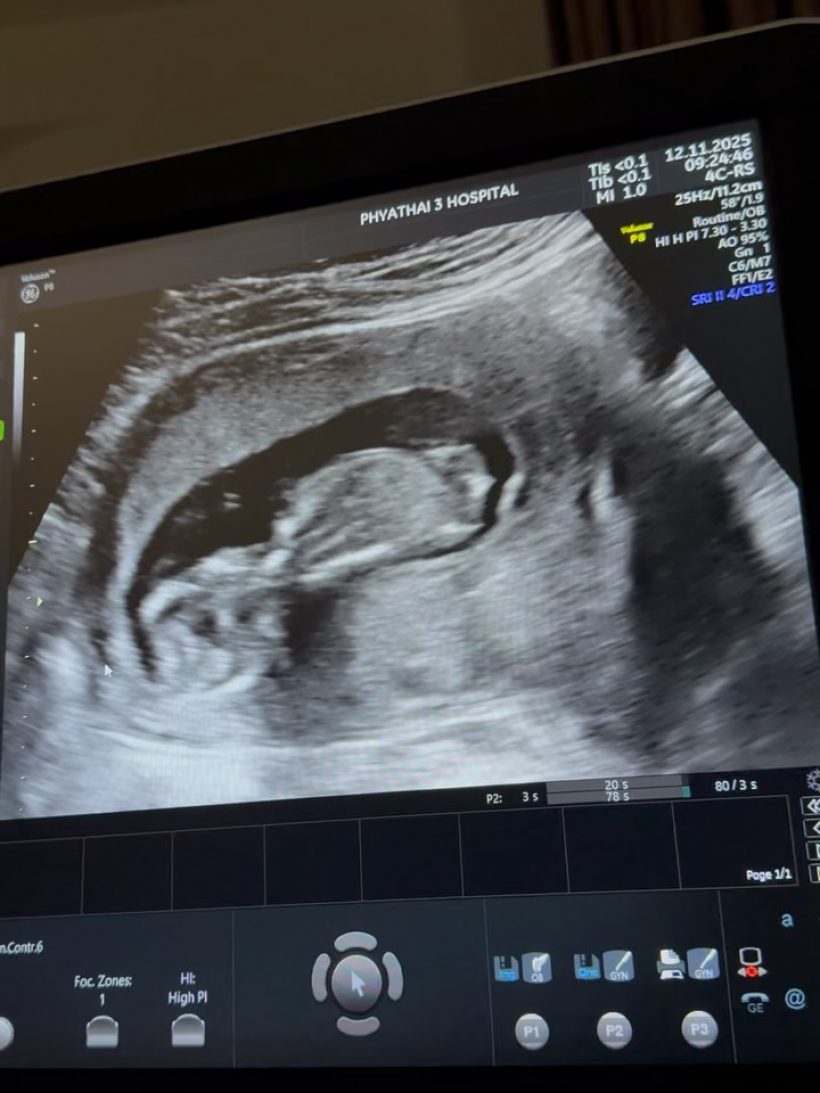

โดยล่าสุด ครูก้อย โพสต์อินสตราแกรม @natcha_loychusak เผยเข้ารับการเย็บปากมดลูกแล้ว เป็นเคสปากมดลูกสั้น ป้องกันการคลอดก่อนกำหนด ขณะกำลังตั้งครรภ์ได้ 12 สัปดาห์